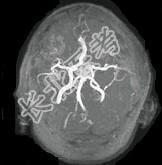

- 单项选择题男性,55岁, 头痛一年余,两个小时前突然出现剧烈头痛, MRI检查如图所示,最可能的诊断为 ( )

E、动脉瘤